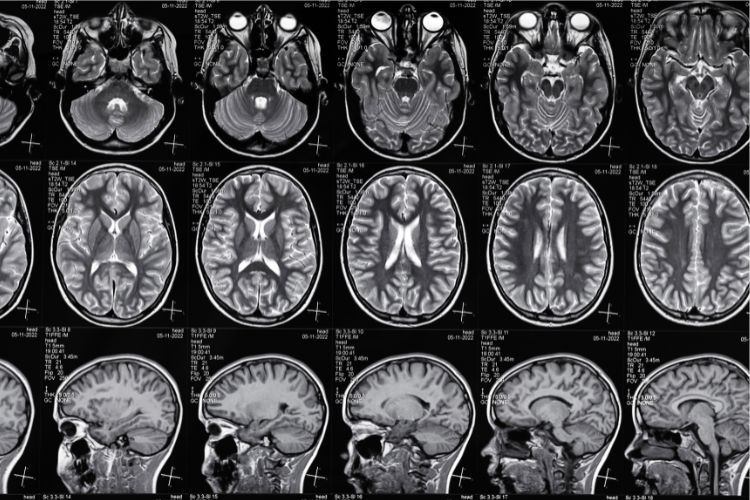

Snimanje mozga:

• Magnetna rezonanca (MR) : MR snimak može otkriti oticanje mozga, upalu ili lezije specifične za određeni uzrok encefalitisa.

• Kompjuterska tomografija (CT) : CT skeniranje se koristi kada MR nije dostupno ili je kontraindikovano. Takođe može pokazati oticanje ili druge strukturne abnormalnosti u mozgu.